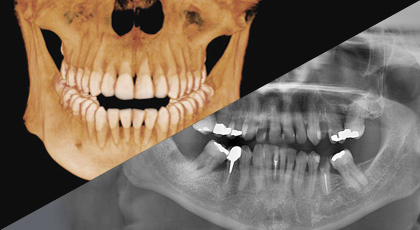

一个绿色智能的扫描不仅可以给你一份CT图像,还可以有一张全景效果的影像。这意味着患者不需要进行两次X光扫描,CT和全景图像还能同时在一个界面上显示。

VATECH已经打破了许多牙科影像的惯例。人们一直认为,金属伪影会导致劣质的影像质量,然而这问题始终无法解决。现在,ART-V可以有效减少金属伪影,使得图像质量更有诊断价值。